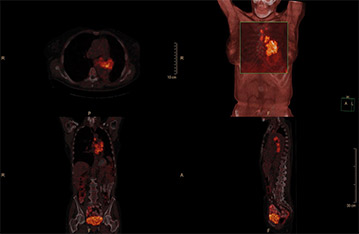

Mit ×Sharp auf dem Ingenuity TF PET/CT erfasste Bilder zeigen Läsionen und Organgrenzen dank Auflösungsrückgewinnung mit hohem Kontrast an.

×Sharp modelliert und korrigiert die Auswirkungen der Point-Spread-Funktion (PSF) des Scanners. Dies führt zu einer Auflösungskompensation und einer höheren Bildschärfe bei den rekonstruierten Ingenuity PET/CT-Bildern. Der Prozess basiert auf der leistungstechnisch effizienten, iterativen Richardson-Lucy-Dekonvolution, die Partialvolumeneffekte in PET-Bildern korrigiert.

Die Auflösungsrückgewinnung kompensiert einen Teil der systemeigenen Auflösungsvarianz im 3D-Raum und ermöglicht so Bilder mit größerer Treue zum Scan-Objekt.